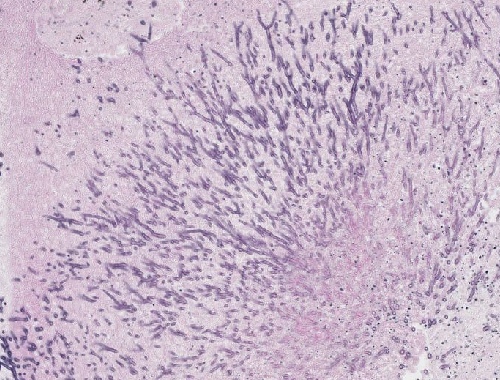

A79: Aspergillus-Pneumonie

• Organdiagnose: Lunge

• Wachstum (dichotom): in Form von Hyphen, die ein Myzel bilden

• PAS-positiv

• “Fruchtköpfchen” – sie entstehen am distalen Ende der Hyphen bei genügender Sauerstoffzufuhr

• “Sterigmen” – sie ordnen sich kranzförmig um eine Verdickung an und können sich vereinzelt ablösen.